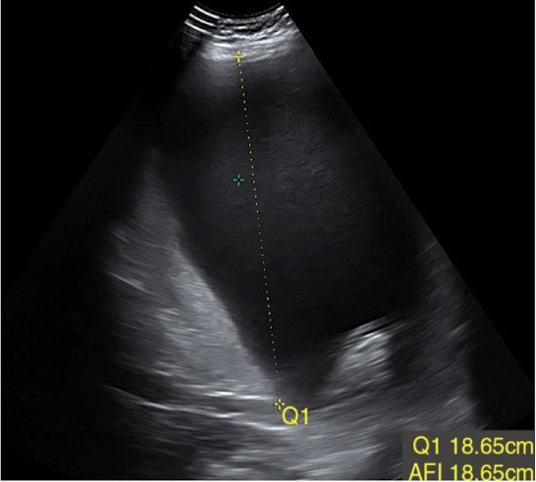

abnormal AFI values

oligohydramnios (too little)

AFI < 5 cm

polyhydramnios (too much)

AFI > 24 cm